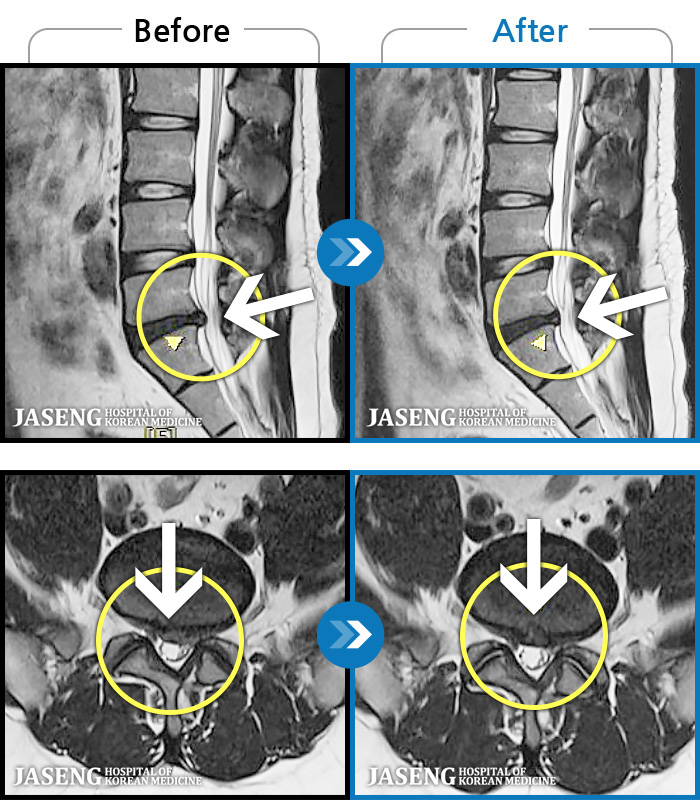

MRI ġ

1,237 MRI ũ ʸ Ȯϼ.